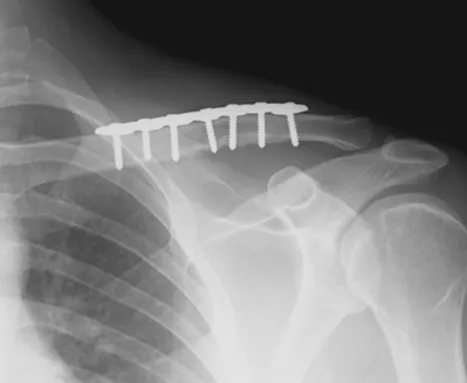

開放性復位內固定手術:器械將骨頭復位並使用螺釘、鋼板、釘子等固定器材將骨頭固定在正確的位置。